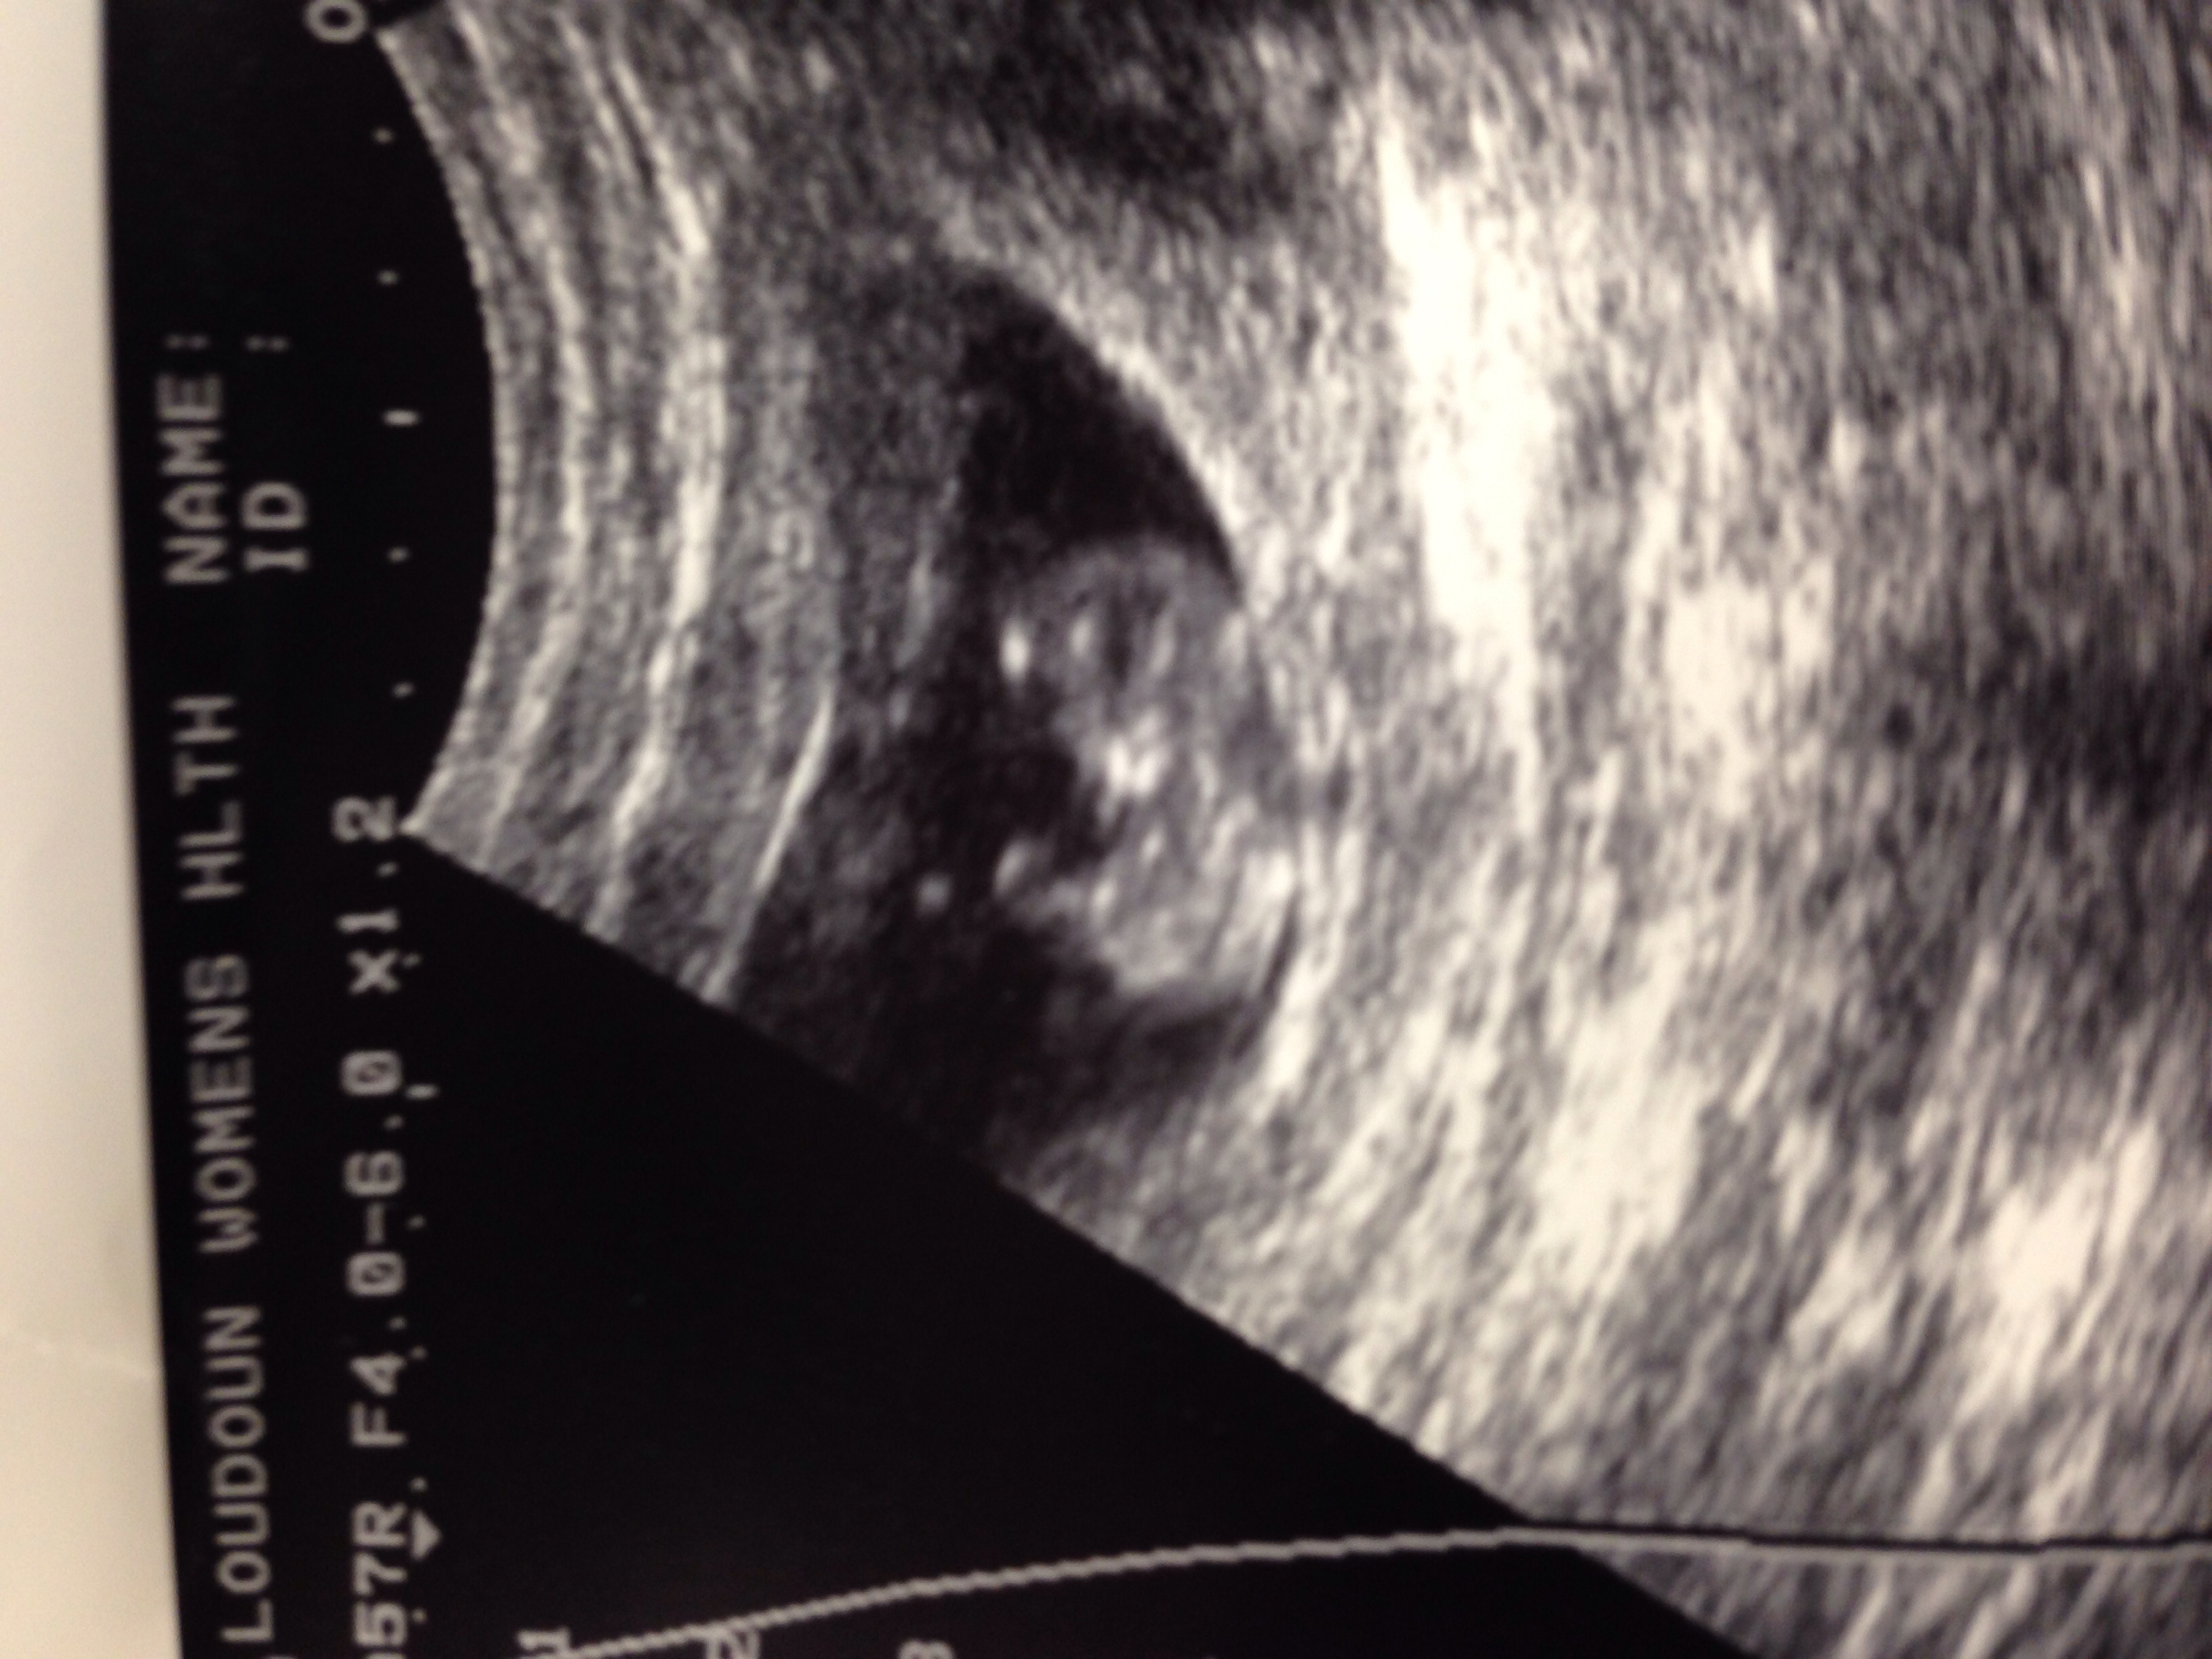

I know it's too early but based on any theories just for fun do you have guesses as to gender? Thanks!Attachment 21911